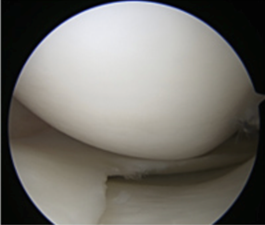

半月板損傷

半月板は大腿骨と脛骨の間にある軟骨組織で、膝にかかる衝撃を和らげる機能や膝の安定性に寄与します。内外側それぞれ1つ存在しています。膝にスポーツや外傷などで強い外力が加わると半月板が損傷してしまいます。そして残念ながら、一度損傷した半月板は自然には治癒しません。

半月板は衝撃を和らげる機能や膝の安定性に関与するため縫合することが望ましいですが治癒する確率が低いと考えられる場合は切除術を行います。

手術方法はともに関節鏡を用います。膝の前面に5mm程の傷を2箇所作り、関節鏡用の道具を用います。